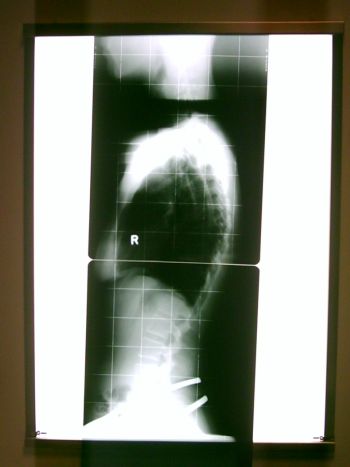

Meine Tochter und ich wurden nach 2-minütiger Wartezeit geröngt, und nach weiteren 10 Minuten im Wartezimmer direkt zu Dr.Hoffmann reingerufen.

Meine Kyphose beträgt 48° und meine Beinlängendifferenz 1 cm. AHA!

Das Röntgenbild...genial!

PHTO0033.JPG (26.53 KiB) 16751 mal betrachtet